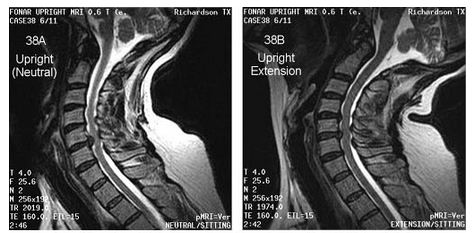

A 62-year-old woman seeking the cause of her chronic radiating neck pain of 30 years duration underwent a weight-bearing flexion-extension MRI in the FONAR UPRIGHT Multi-Position MRI. Her neutral-sitting examination showed a C5-6 herniation, but her UPRIGHT® cervical extension examination visualized an additional herniation at C4-5 that altered plans for a simple discectomy and fusion at C5-6.